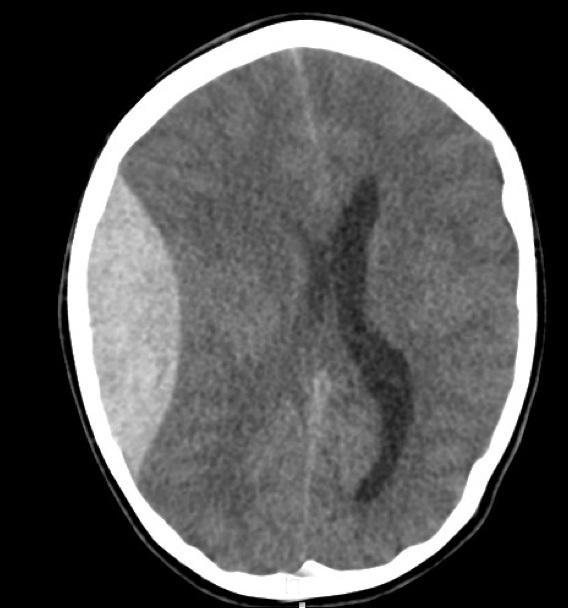

Chronic Subdural Haemorrhage

Il y a 7 ans